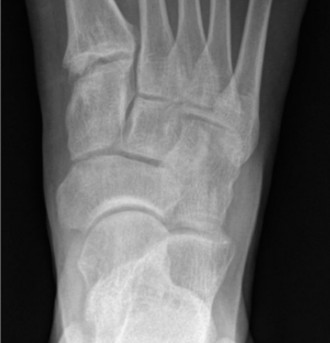

- Radiographs (X-rays): Essential initial imaging.

- Weight-bearing anteroposterior, lateral, and oblique views of the foot and ankle are standard.

- Lateral Pain: May show fifth metatarsal base fractures (Jones, avulsion), cuboid subluxation, calcaneal stress fractures, or signs of chronic ankle instability (e.g., osteophytes, subtle widening of talar tilt).

- Radiographs (X-rays): These are the initial imaging modality for nearly all foot and ankle complaints.

- Standard views: Weight-bearing anteroposterior (AP), lateral, and oblique views of the foot are crucial to assess alignment, osseous integrity, and degenerative changes. Ankle views (AP, lateral, mortise) should be included if ankle pathology is suspected.

- Weight-bearing lateral view: Critical for assessing arch height, talonavicular sag, Meary's angle (talus-first metatarsal angle), calcaneal inclination, and identifying hindfoot valgus in pes planovalgus deformities.

- Saltzman view: A hindfoot alignment view quantifying hindfoot valgus or varus.

- Lateral Foot Pain Imaging Insights: May identify fifth metatarsal base fractures (Jones, avulsion), cuboid subluxation, calcaneal stress fractures, or signs of chronic ankle instability such as osteophytes, subtle talar tilt, or impingement. Stress radiographs can quantify talar tilt and anterior drawer, though their utility is debated for chronic instability.